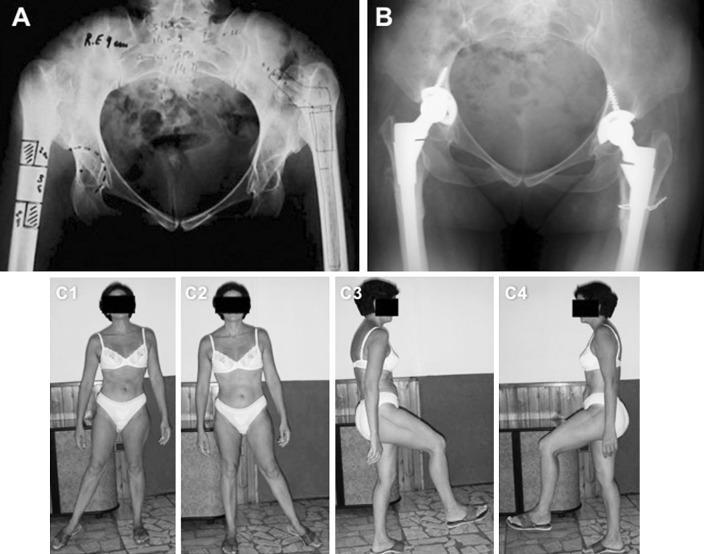

Total hip replacement for high dislocation of the hip presents some difficulties, considering patients' young ages, the abnormal hip anatomy and the high rate of complications. In this study, we present our experience in terms of clinical and radiological results in the treatment of Crowe type IV hips with subtrochanteric femoral shortening osteotomy and cementless total hip replacement.

We retrospectively reviewed 15 patients with Crowe type IV hip dysplasia (two bilateral cases for a total of 17 hips) treated with cementless total hip replacement associated with shortening subtrochanteric osteotomies (nine transversal and eight Z-shape osteotomies) between March 2000 to February 2006. The mean follow-up was 88 months (range 63-133). Harris hip score, leg length discrepancy, neurological status, union status of the osteotomy and the component stability were the criteria of the evaluation. All complications were noted.

RESULTS

The mean HHS improved from 38.3 (range 32-52) to 85.6 (range 69-90). The mean preoperative leg length discrepancy was of 45 mm (range 38-70) and reduced to a mean of 12 mm (range 9-1.6) postoperatively. All osteotomies resulted healed at an average of 12.3 weeks (range 10-15). No cases of delayed union or nonunion were detected. Two patients (11%) showed early symptoms of sciatic nerve palsy which resolved uneventfully in 6 months. There was no migrations and none of the implants required revision.

CONCLUSIONS

Cementless THA with shortening subtrochanteric osteotomy is an effective method in the treatment of patients with Crowe type IV development dysplasia of the hip.